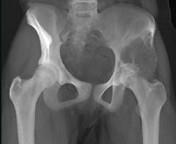

问题 女,31岁,左侧髋部疼痛1月余,有压痛,压之有捏乒乓球感,请结合影像学检查,选出最可能的诊断()

选项 A.骨囊肿 B.骨巨细胞瘤 C.动脉瘤样骨囊肿 D.成软骨细胞瘤 E.骨结核

答案 B